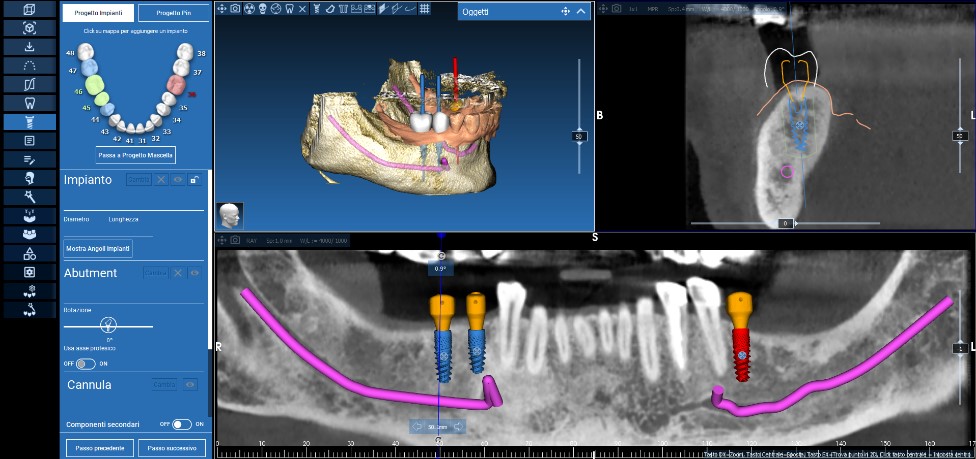

Già in prima visita si procedeva alla rilevazione di una scansione intraorale con scanner TRIOS 3 (3SHAPE, Copenhagen, Danimarca) e all’esecuzione di una CBCT (NewTom, Cefla, Bologna, Italia) per la raccolta di tutti i dati utili alla realizzazione di una progettazione computer assistita. I dati DICOM e i file Stl venivano dunque importati in un software di pianificazione digitale (REALGUIDE Software Suite, 3DIEMME, Cantù, Italia). Il software permetteva come prima cosa l’identificazione del nervo alveolare inferiore, sia di destra che di sinistra, garantendo la pianificazione dell’intervento in massima sicurezza.

Successivamente, dopo l’esecuzione di una ceratura diagnostica digitale, veniva identificata la posizione corretta dove inserire i tre impianti. A questo punto veniva stabilito quale tipo di iPhysio® utilizzare per ogni singolo impianto: queste particolari viti di guarigione, infatti, possono essere scelte in base alla tipologia dell’elemento da sostituire, e allo spessore del tragitto transmucoso, offrendo i vantaggi sia degli abutment customizzati che di quelli commerciali (Figura 3).

Fig. 3. Ceratura e progetto digitale di posizionamento implantare e delle viti di guarigione.

Ultimati questi passaggi, si passava alla progettazione di una dima chirurgica a supporto dentale realizzata con tecnologia Polyjet (Stratasys, Rehovot, Israele), in modo da trasferire chirurgicamente in maniera pianificata e guidata, dal virtuale al reale, la pianificazione realizzata sulla piattaforma software (Figure 4, 5, 6, 7).

Fig. 4. Pianificazione della dima chirurgica a supporto dentale.